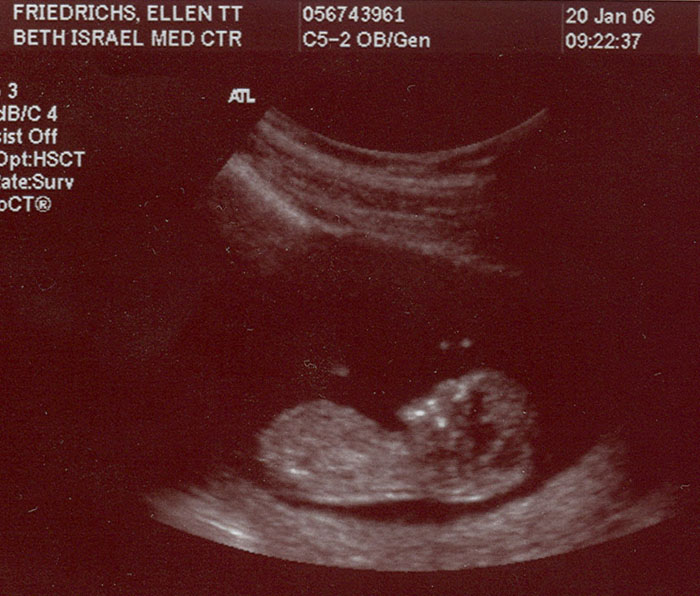

Making progress - 20 weeks- March 16 - 2006

A foot